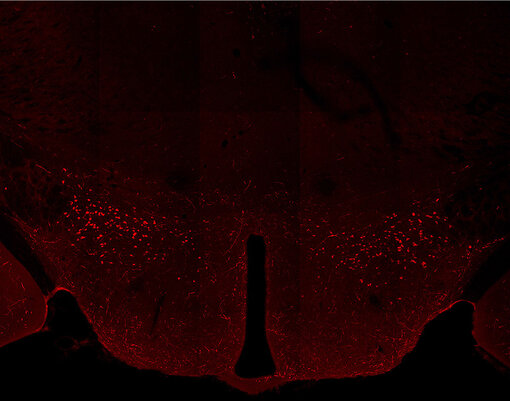

Indirect immunostaining of PFA fixed WT mouse

Indirect immunostaining of PFA fixed WT mouse brain section (hypothalamus) with Guinea pig anti-Orexin A (cat. no. 389 004, dilution 1:500 red).

Courtesy: Dana Mayer & Markus Fendt, Institute of Pharmacology and Toxicology, Magedeburg